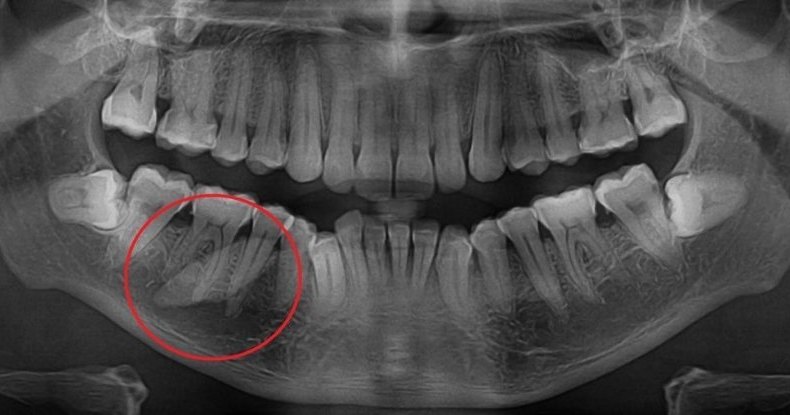

Сиалолиты — это кусочки кальция, которые постепенно обрастают налетом и залегают в мягких тканях ротовой полости. Чаще всего они образуются в слюнных железах, поэтому в народе их называют «слюнными камнями». Это мелкие, но неприятные образования, которые могут спровоцировать воспаление. Страдают от них преимущественно люди от 50 лет и старше, у которых из-за возрастных изменений организма начинаются проблемы с активностью желез.